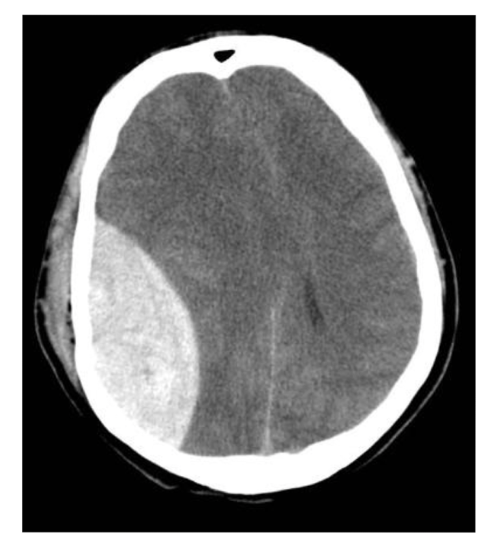

What is the protocol + pathology?

• CT non con brain

• Intraparenchymal

haemorrhage: brain bleed within the brain parenchyma

• Hyperattenuating mass posteriorly in the occipital lobe

• Midline shift

• Adjacent oedema.